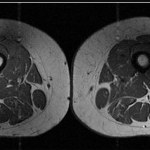

Ludzkie udo jak marmurkowy stek. Przetworzona żywność zmienia nasze ciała

Dieta bogata w wysokoprzetworzone produkty powoduje odkładanie się w mięśniach tłuszczu do tego stopnia, że ludzkie uda zaczynają wyglądać jak marmurkowe steki. Tłuszcz odkłada się...zdrowie, mięśnie -